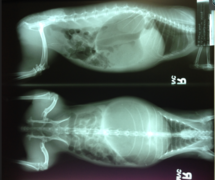

Acute gastrointestinal dilation

Acute gastrointestional dilation is a syndrome in which the stomach suddenly expands (dilates) due to excess gas and fluid. The condition is more commonly known as bloat in rabbits but is also called gastric dilation, gastric dilatation, and intestinal obstruction.

- progressive abdominal distension